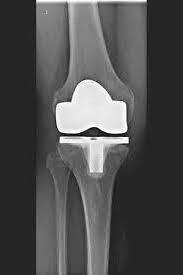

L’articulation artificielle du genou remplace la surface cartilagineuse détruite par l’arthrose. L'os sous-jacent du fémur et de la tête tibiale reste intact. Certains comparent une articulation artificielle moderne du genou à un couronnement de dent ; le terme exact est ce qu'on appelle le resurfaçage bicondylien. Entre les nouvelles surfaces sur la partie supérieure et inférieure de la jambe se trouve ce que l'on appelle une incrustation en plastique blanc spécialement durci, qui peut être vue sur l'image radiographique comme la distance entre les pièces métalliques.

Les articulations artificielles du genou sont appelées prothèses complètes et prothèses partielles. Je vérifie soigneusement au préalable quelle prothèse vous convient sur la base de l'examen clinique, ainsi que sur la base d'images radiographiques ou IRM.